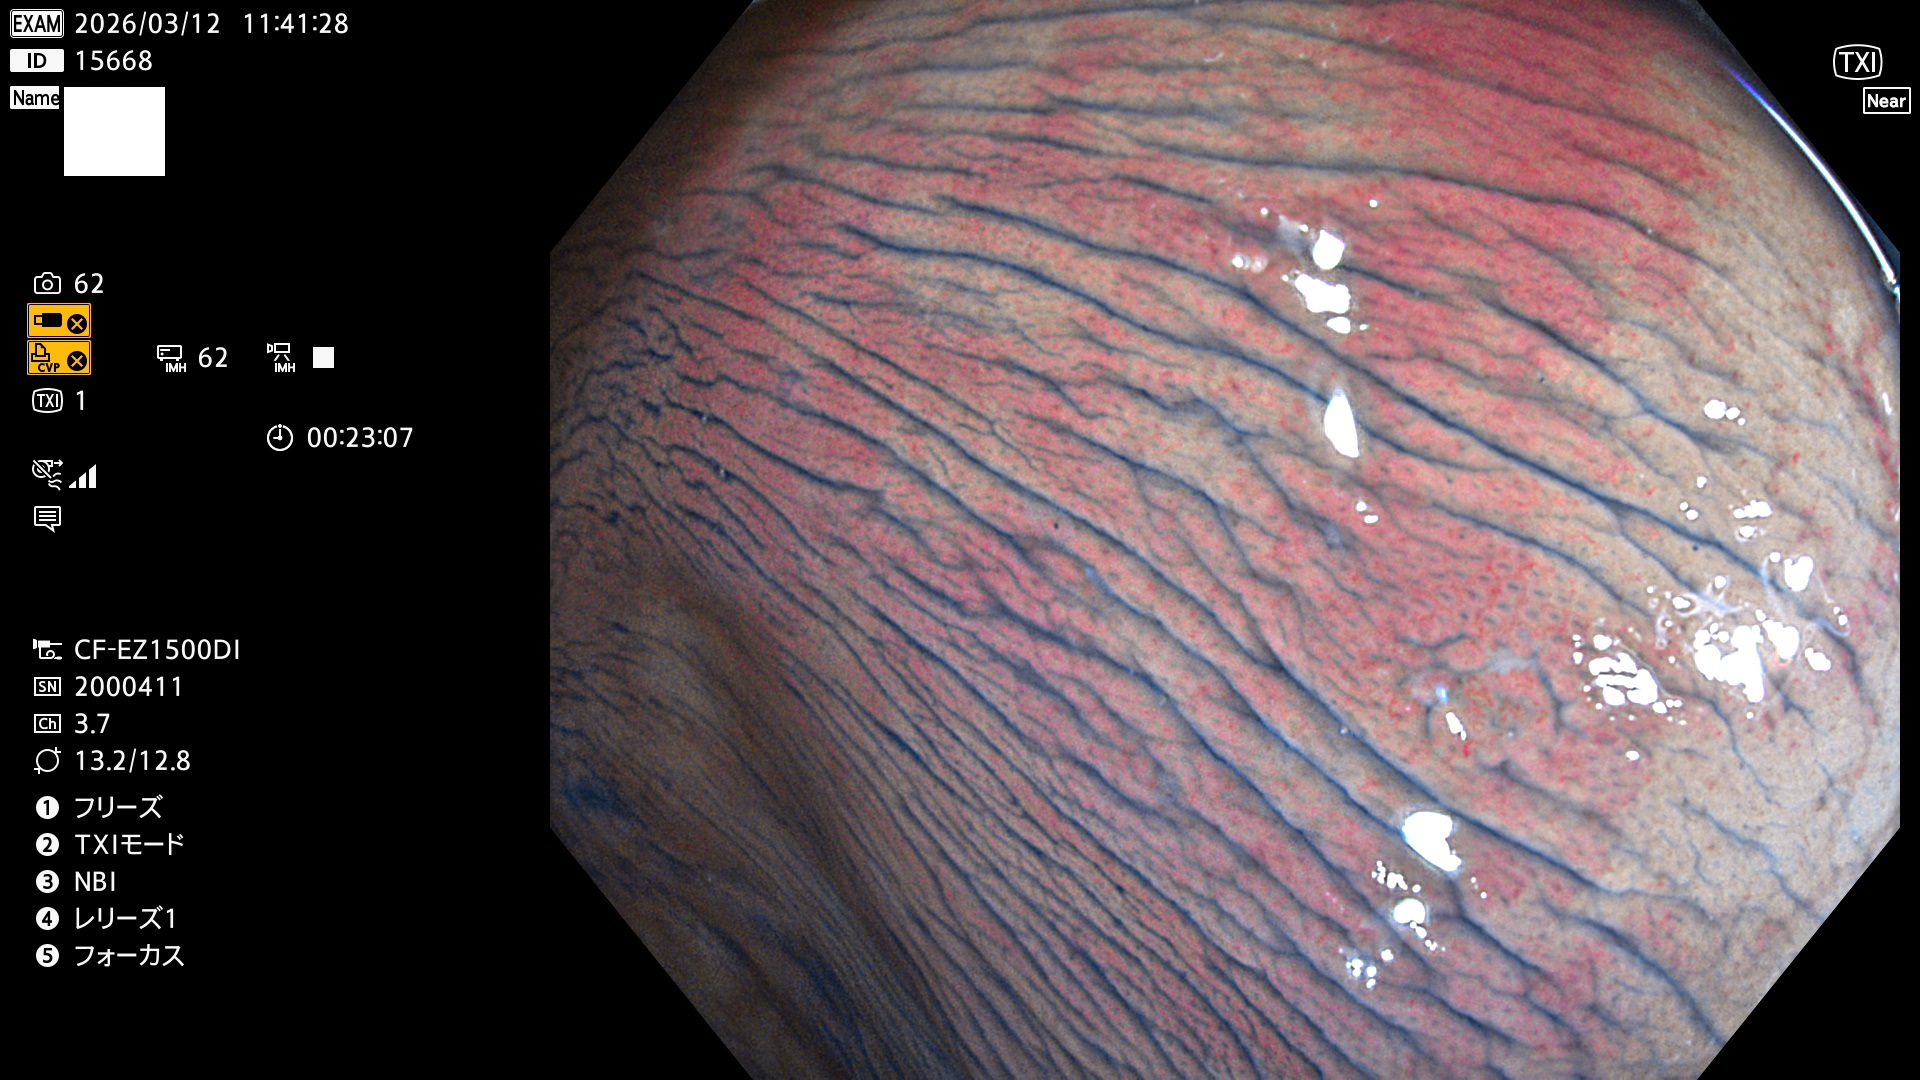

毎週の検査(木・金・土・日)に発見されたUbとUc型・腺腫を、その週の日曜の夜にUPし1週間、提示します。

2026年3月12日〜3月15日の4日間(40件)6個 (Uc_ADR=6個/40人=15%)